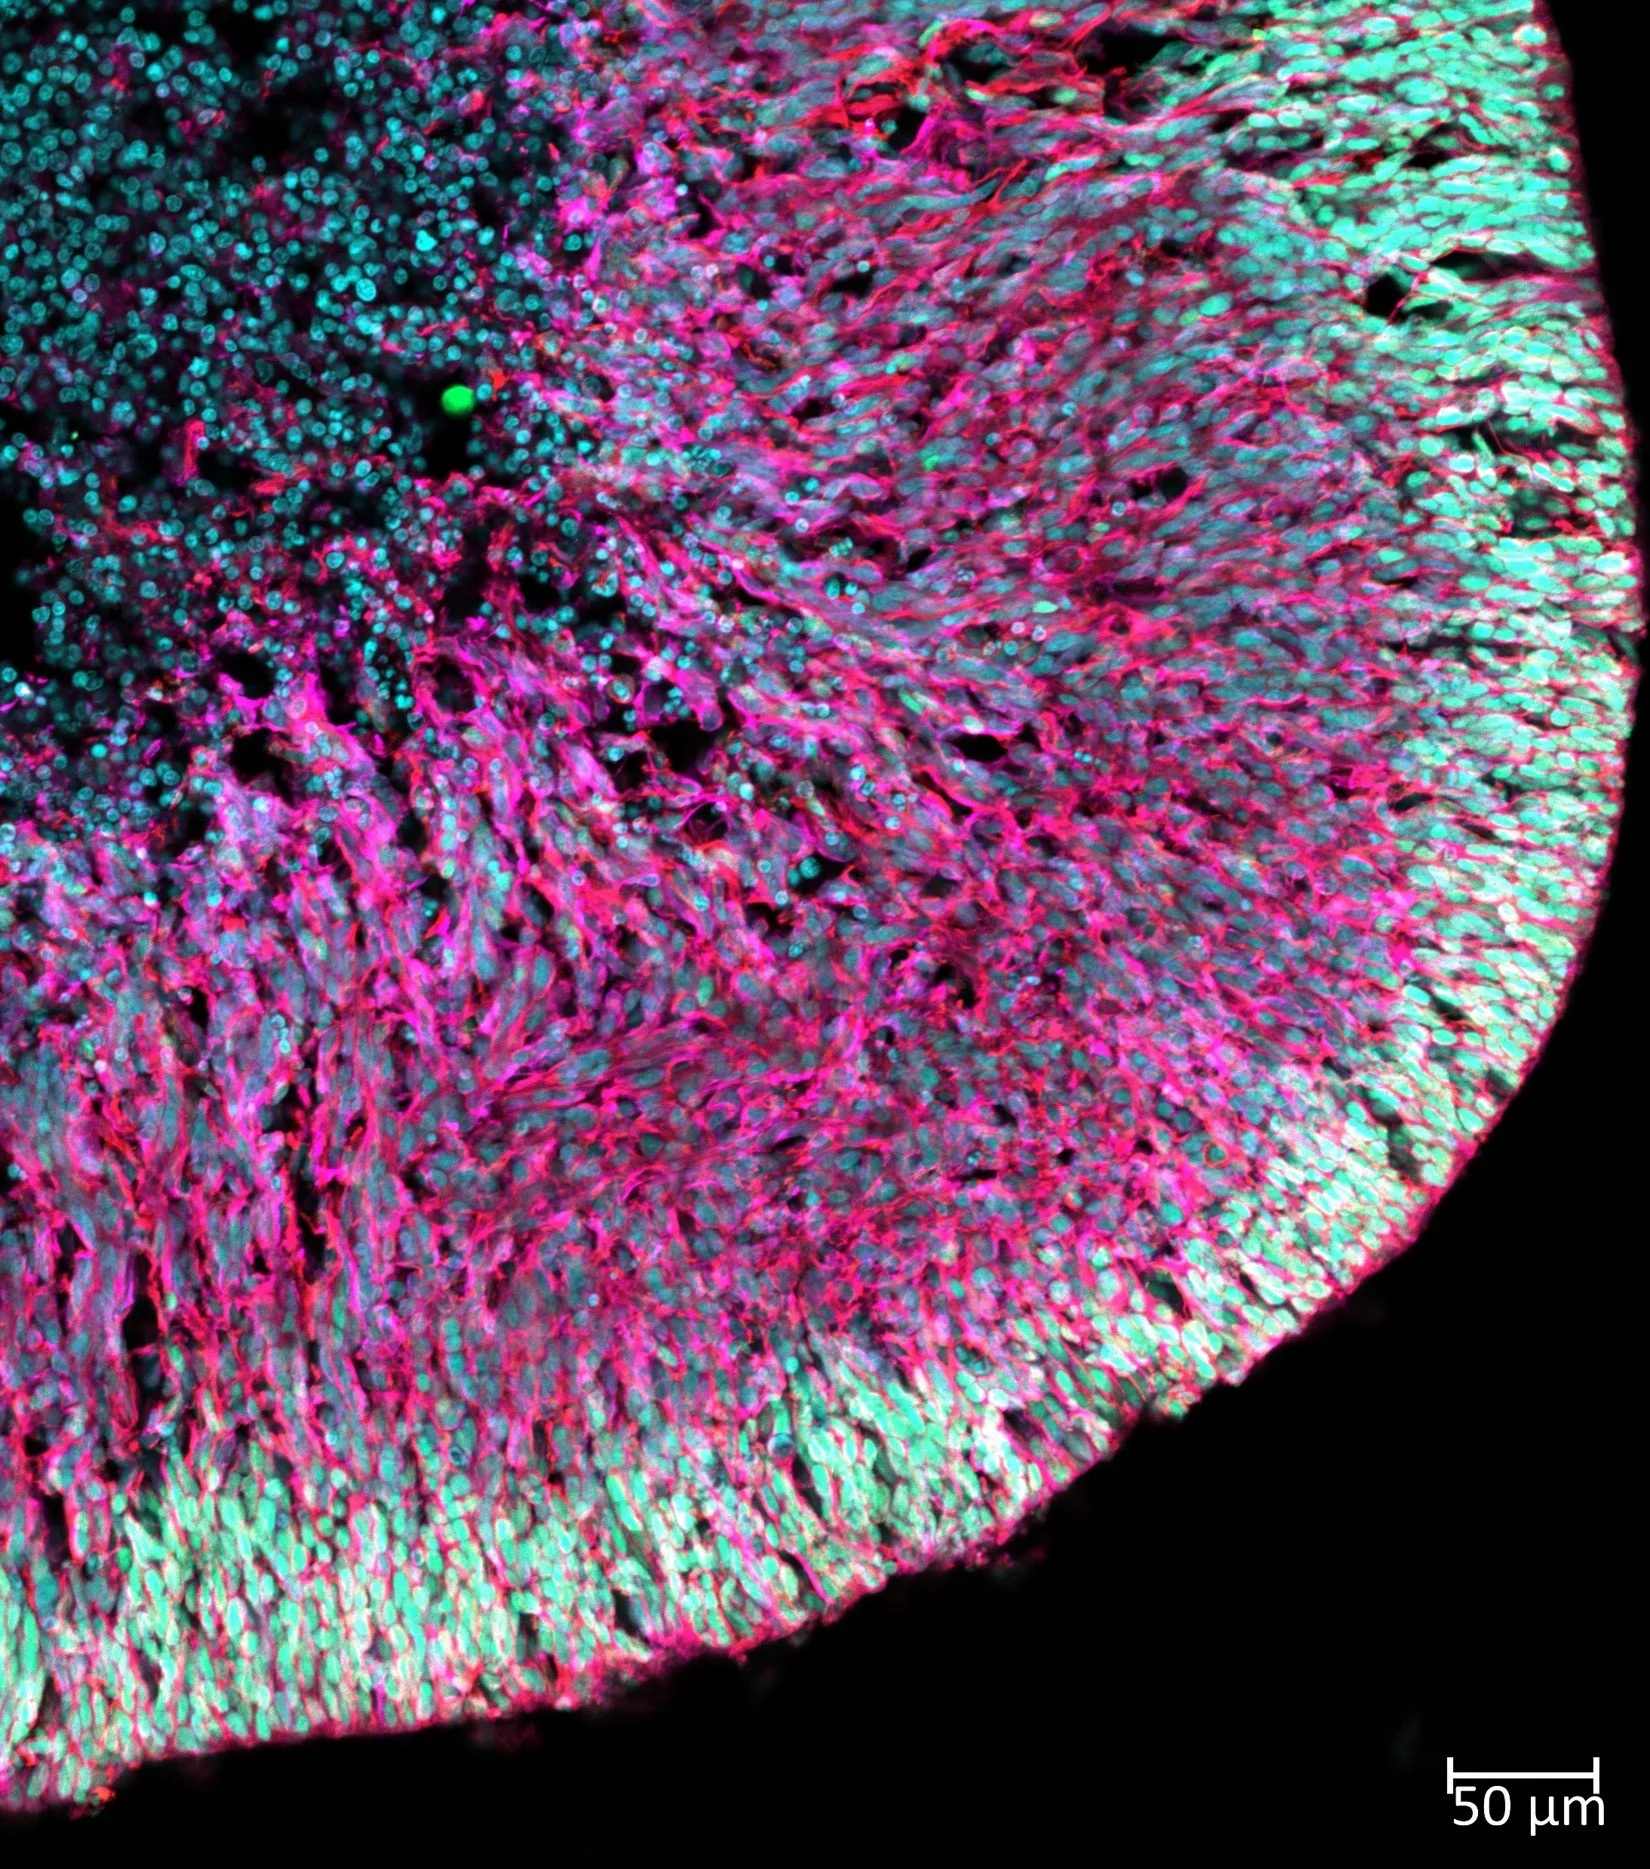

Our research focuses on developing predictive, human-relevant in vitro models using iPSC-derived brain organoids and microphysiological systems to advance developmental neurotoxicology, gene × environment interactions, and disease modeling. We study the molecular mechanisms of cellular responses to environmental stress and their impact on brain development, connectivity, and function. By modeling learning and memory processes, synaptic plasticity, and neuroimmune interactions—such as through our microglia-integrated organoid (μbMPS) platform—we aim to create scalable systems that bridge fundamental neuroscience, environmental health, and translational research, moving toward more mechanistically informed and human-centered approaches to brain science.